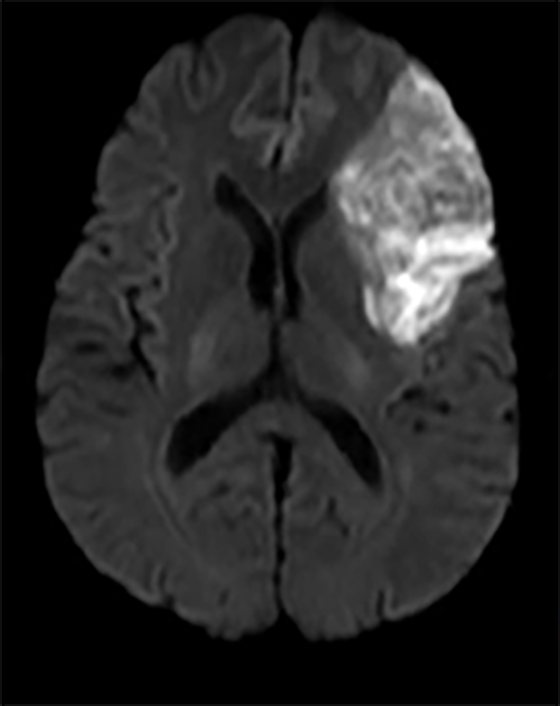

Deși unele tipuri de infarct sunt aparente pentru ochiul liber neprofesionist (Fig.2), altele sunt mai subtile și mult mai reduse în intensitatea aparentă și dimensiune (Fig.3 & Fig.4).

În imaginile din figurile 2-4 se pot vedea cu ochiul liber abnormalitățile la nivelul creierului din imaginile RMN. Astfel de cazuri reprezintă o parte importantă din setul de date, iar restul imaginilor e compus din cazuri mult mai greu de identificat sau clasificat chiar și pentru radiologii cu experiență. Pentru moment suntem departe de a concura cu precizia și acuratețea radiologilor, dar soluțiile de detecție automată de astfel de leziuni vor să vină în ajutorul medicilor. Un medic radiolog interpreta în jur de 679 imagini de tip RMN per zi în anul 2010 [9]. De atunci cantitatea de imagini produse de aparatura medicală e în continuă creștere iar presiunea asupra radiologilor crește și ea, iar cu aceasta cresc și șansele de eroare sau de ratare a unor leziuni importante. O soluție automată vine ca un adjuvant pentru radiolog asigurându-se că acestuia nu îi scapă niciun caz clar de leziune, iar radiologul se poate axa pe cazurile cu adevărat dificile și importante. Și în plus, un algoritm nu suferă de oboseală și nici nu necesită repaus.

Fig. 4 SImulare de detecție infarct cerebral din RMN-DWI. Ref: [8]